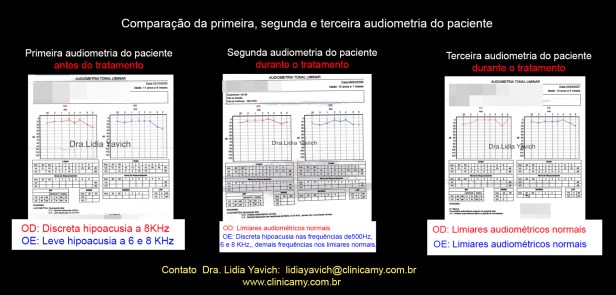

A primeira audiometria do paciente revela uma discreta hipoacusia no ouvido esquerdo e uma leve hipoacusia no ouvido direito.

A segunda audiometria do paciente revela limiares normais no ouvido esquerdo e uma discreta hipoacusia no ouvido direito.

Comparação da primeira e a segunda audiometria do paciente durante o tratamento.

Normalização dos limiares no ouvido direito e melhora nos limiares do ouvido esquerdo.

A terceira audiometria do paciente revela limiares normais no ouvido esquerdo e limiares normais no ouvido direito.

Comparação da primeira, segunda e terceira audiometria do paciente durante o tratamento.

Normalização dos limiares no ouvido direito e normalização dos limiares do ouvido esquerdo.